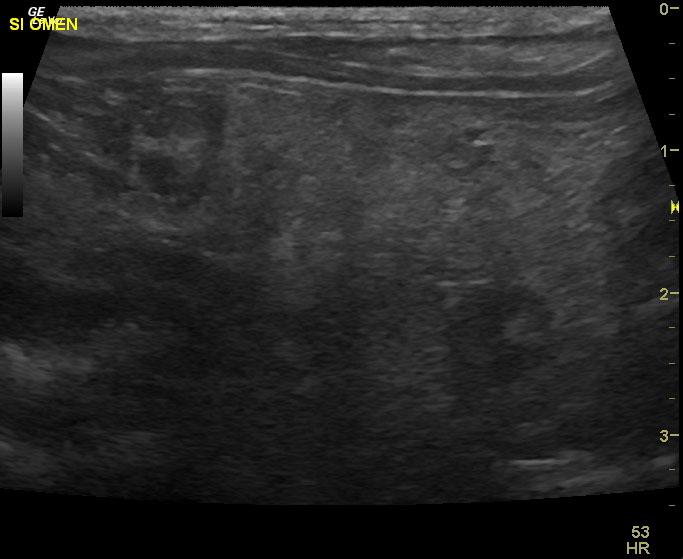

A 9 year old MN Maltese dog was presented for evaluation of progressive anorexia and soft feces. Physical examination and rectal palpation were both within normal limits. Fecal and urinalysis, CBC, serum biochemistry, cPl, and survey radiographs of the thorax and abdomen were all within normal limits.